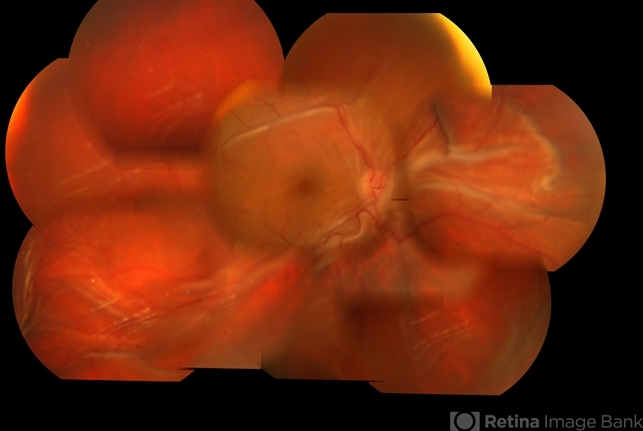

- choroidal folds

- Fundus photo of a 32-year-old male presenting with post traumatic choroidal folds and hypotony.